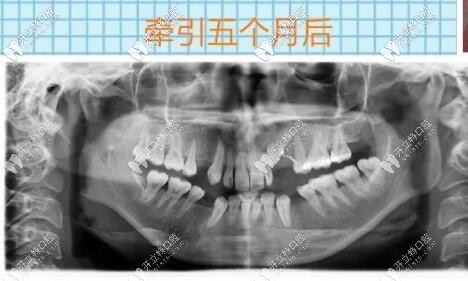

埋伏牙開窗牽引5個(gè)月后

導(dǎo)萌手術(shù)結(jié)束之后的幾個(gè)月以后,逐漸迎來了曙光,看到了埋伏牙逐漸牽引出來,那種激動(dòng)的心情無法言語,時(shí)間過去太快了,到目前為止仍不后悔當(dāng)初的決定。